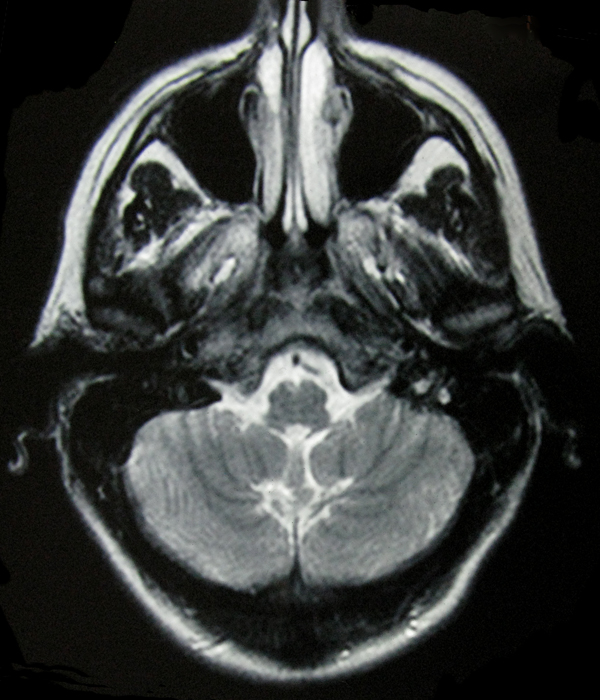

- My Brain in 2009